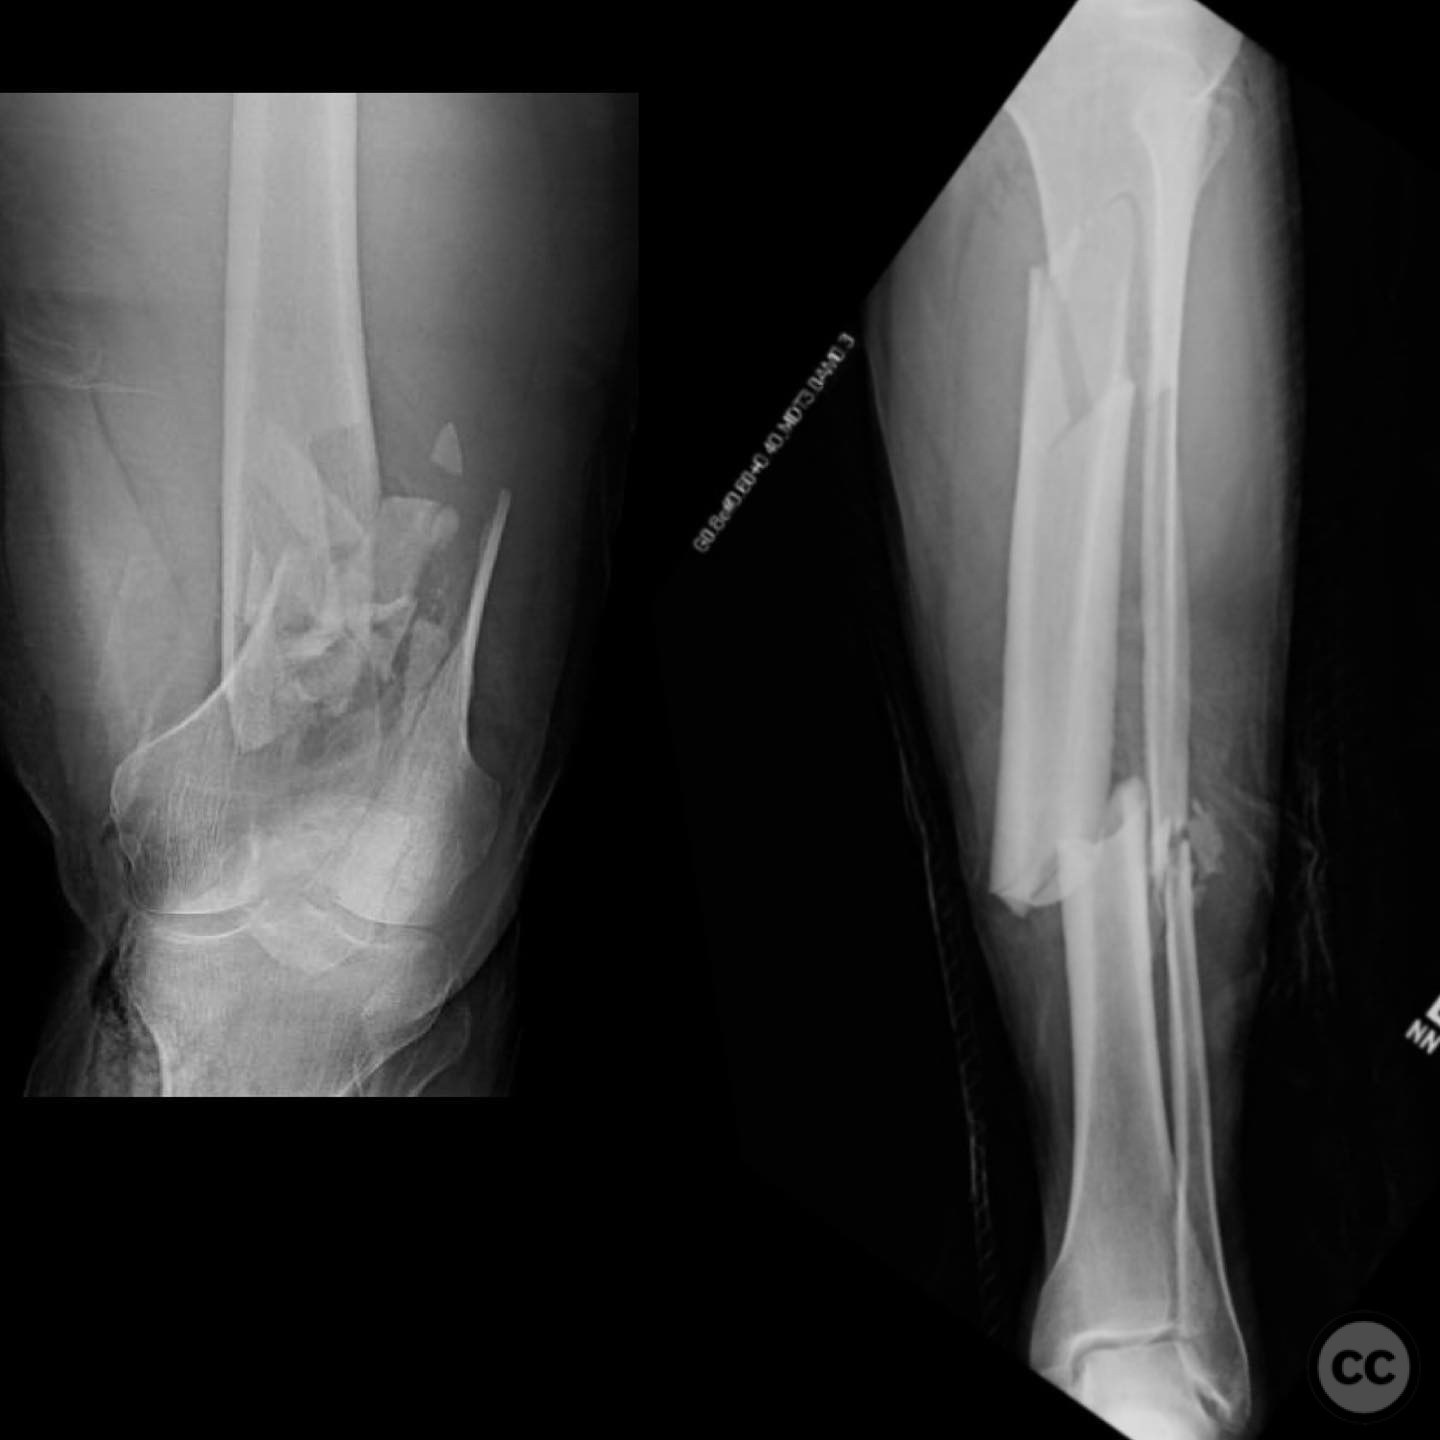

Clinical and radiological findings:  A 44-year-old male cyclist was involved in a collision with a car, resulting in open fractures of the distal femur and segmental tibia. The femoral fracture presented with a 4 cm transverse wound on the anterior aspect, while the tibial fracture had a 2 cm anterolateral wound at the distal site. There were no associated head, chest, or abdominal injuries, and compartment syndrome was not present. Vascular examination was unremarkable.

Planning remarks:  The preoperative plan involved initial debridement and irrigation of both open fractures. The tibia was prioritized for intramedullary nailing, followed by spanning external fixation of the distal femur. Definitive fixation of the distal femur was planned for two days post-initial stabilization.